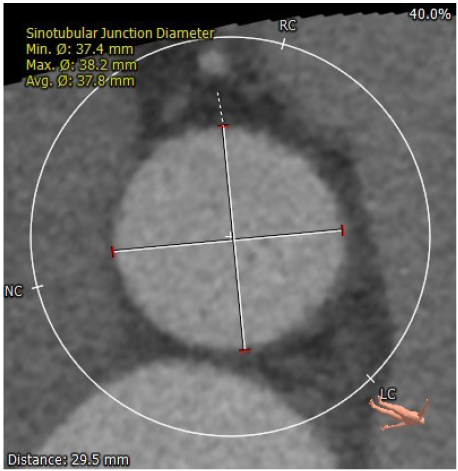

瓣环直径26.7

左室流出道直径:30.8

升主动脉增宽

冠脉高度尚可。左冠高度:13.4,右冠高度:20.6。心脏角度52

1. 瓣膜型号及球囊:瓣环26.7mm,左室流出道30.8mm,考虑32VenusA Plus瓣膜,

2. 冠脉风险:结合窦部大小大,stj高度和直径,冠脉风险小